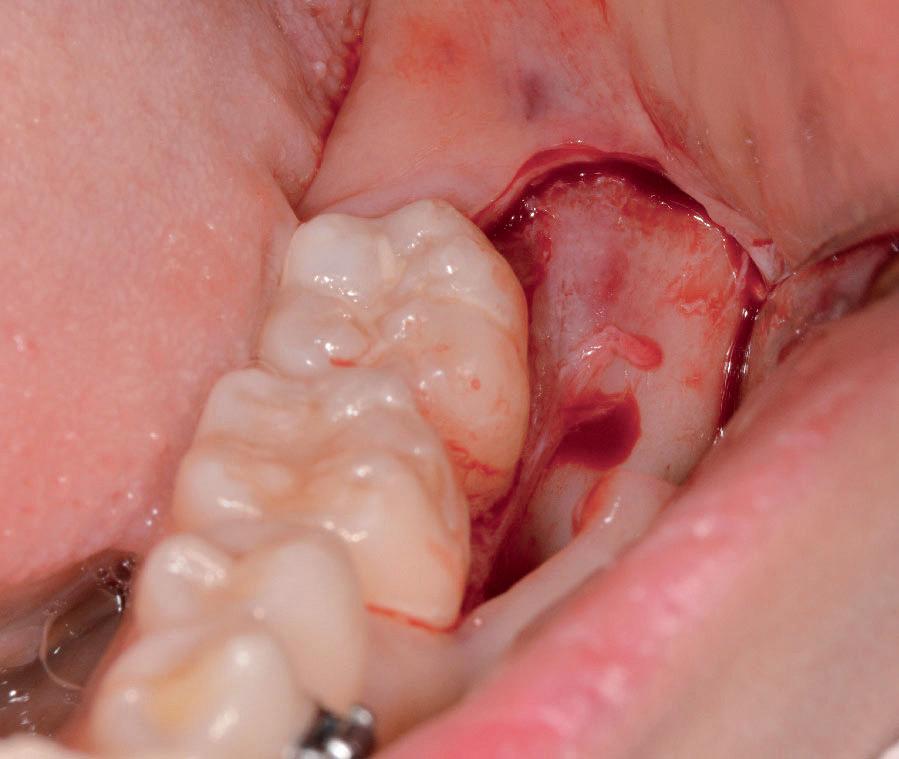

In generale l’estrazione di un dente del giudizio inferiore, utilizzando il manipolo dritto, richiede un’incisione posteriormente alla superficie mesiale del secondo molare. Se il dente non è incluso, la rimozione di osso vestibolare non è necessaria, ma al contrario, più il dente è in profondità e più osso vestibolare dovrà essere rimosso. Una volta che l’osso vestibolare è stato rimosso, il dente viene sezionato vestibolo-lingualmente e separato in una metà mesiale e una distale, utilizzando una leva. Il segmento distale del dente che non giace nel sottosquadro della regione distale del secondo molare viene rimosso per primo e poi viene rimosso quello mesiale. Figg. 150-156